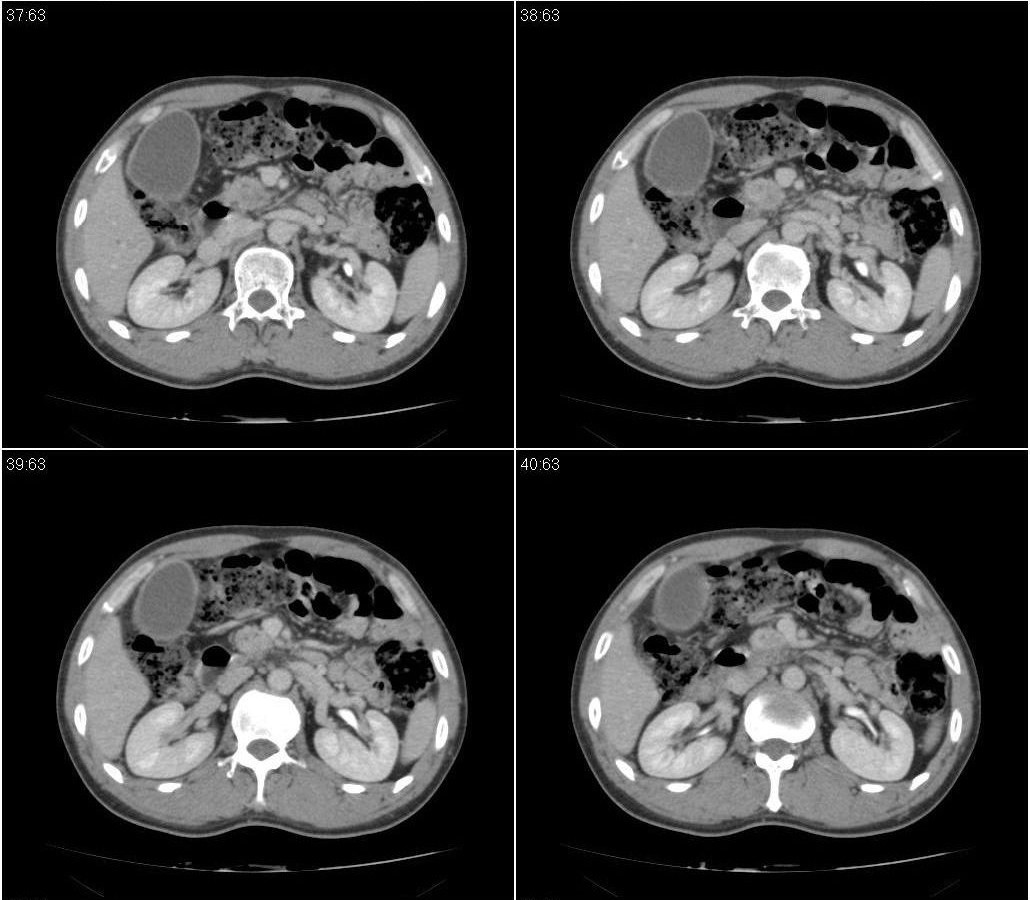

标题: CT21384:男性,50岁。发现无痛性黄疸十余天,B朝提示肝胆管 [打印本页]

标题: CT21384:男性,50岁。发现无痛性黄疸十余天,B朝提示肝胆管

1.考虑:壶腹占位病变(癌?)。

2.胆系低位梗阻:肝内外胆管扩张,胆囊增大,胰管扩张。

胰头癌伴低位胆道梗阻。

胆系低位梗阻(肝内外胆管扩张,胆囊增大,胰管扩张);考虑胰头癌或壶腹癌所致。

胆总管突然中断,壁增厚且强化,考虑胆总管癌可能性大伴胆系梗阻,胆囊炎

胰头强化欠均匀,胆胰管扩张。考虑胰头癌可能性大。

胆系低位梗阻(肝内外胆管扩张,胆囊增大,胰管扩张,钩突似有占位);考虑胰头癌